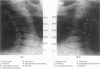

OBJECTIVE: To determine whether a swimmer's view or supine (trauma) oblique views are more likely to visualise the lower cervical spine when a lateral view fails to show the cervicothoracic junction. DESIGN: A prospective study comparing two 20 week periods. In the first phase the swimmer's view was performed as an additional view when the cervicothoracic junction was not demonstrated. In the second phase paired supine oblique views replaced the swimmer's view. RESULTS: 230 patients were included in the first phase, of whom 60 required swimmer's views. In the second phase 62 of 197 patients required supine oblique views. Radiology analysis of 53 pairs of supine oblique views showed that the vertebral bodies were adequately demonstrated at the cervicothoracic junction in only 20 patients (38%) compared with 22 in the swimmer's group (37%). The facet joints and posterior elements were, however, clearly seen in 37 (70%) of the supine oblique patients compared with 22 (37%) of the swimmer's group (p < 0.001, chi2 test). Exposure dose calculations showed a substantial reduction for a pair of supine oblique views (1.6 mGy) over a single swimmer's view (7.2 mGy). CONCLUSIONS: In injured patients for whom the standard three view series fails to demonstrate the cervicothoracic junction, swimmer's views and supine oblique views show the alignment of the vertebral bodies with equal frequency. However, supine oblique films are safer, expose patients to less radiation, and are more often successful in demonstrating the posterior elements.